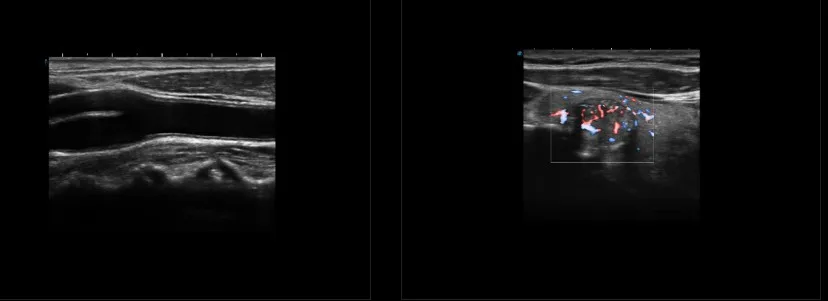

NEW Sonoscape P9 P10 P15 Doppler Trolley Ultrasound Device State of the Art Electronic Equipment